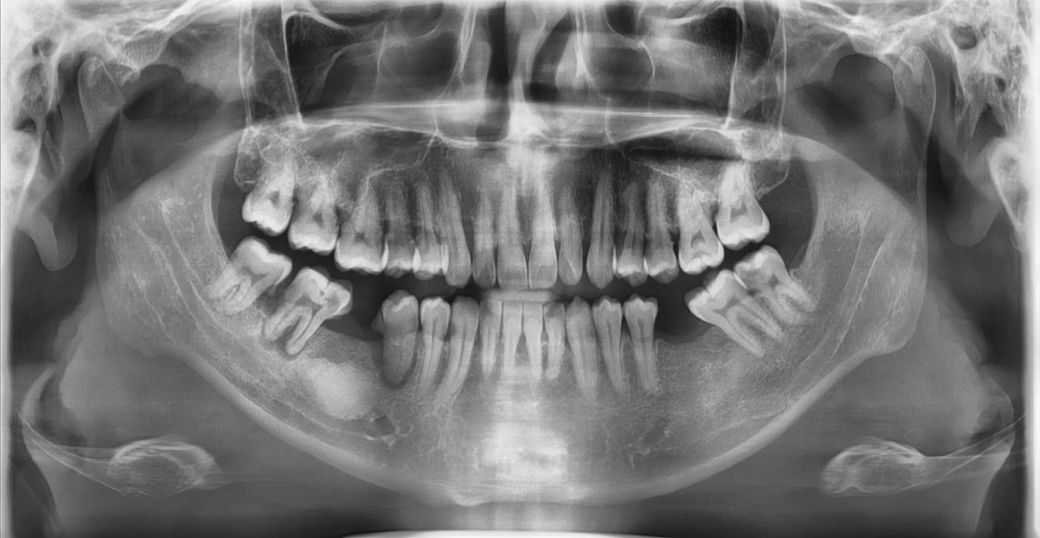

임플란트 질문 치아 엑스레이사진 첨부합니다

-왼쪽 아래 어금니: 충치가 있으며, 일부 병원에서 발치 후 임플란트 2개 권장.

-왼쪽 위 어금니: 충치가 있어 크라운 치료 권장.

-오른쪽 아래 어금니: 충치와 뿌리 염증이 심해 발치 후 임플란트 3개 권장 (일부 병원은 2개 임플란트 + 브릿지 3개로 제안).

-추가 의견: 오른쪽 아래 발치 부위에 뼈이식 필요하다는 소견.

사진상에서 왼쪽 아래 치아들은 발치를 하고 임플란트를 하셔야될것같습니다. 뼈이식의 경우에는 발치하고 기다렷다가 하셔도 될것같습니다. 정확한건 CT를 찍어봐야 알수 잇을것같습니다. 그리고 사진상 오른쪽 아래는 치아가 많이 기울어져 잇어서 임플란트 하나를 심어도 옆에 기울어진 치아는 크라운치료를 해서 공간을 확보해야될것같습니다.

2. 제일 큰 이견은 사진상왼쪽 아래 치아에 대한 치료방법 같은데 5번,7번치아는 신경치료를 시도해볼 순 있을것 같으나 치료성공을 장담하긴 어렵습니다

3. 오른쪽 아래는 염증이 심하니 발치먼저하고 뼈이식 하고 기다리면서 나머지 살릴 수 있는 치아 살리고, 그 뒤 임플란트 하면 됩니다

4. 엠도게인 논리는 현재 질문자 잇몸뼈 상태에 부적절합니다